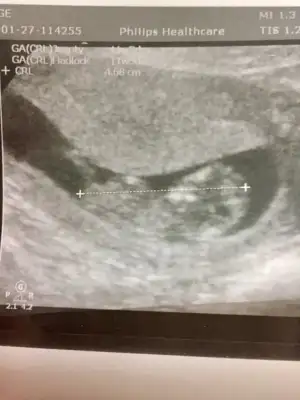

dr soylemeden siz gorun genital nub teorisi ( bebegin cinsiyeti)

13. Haftada kız demiştin canım doktorum da başından beri öyle diyor bugün de öyle dedi. Cikintiyi çizebilir misin 😍

Canım emin değilim en iyi 11 12 13 haftalar olmalı dedim yinede USG ile uğraşıp cizeyim gördüğüm nub ise 🙈

Bu nub değil artık çizdigim organı oluşmuş oluyor yanılmış olabilirim bu haftalar benim alanım degil 🙈 gördüğüm pipi olmayabilir ☺️Eki Görüntüle 2770911